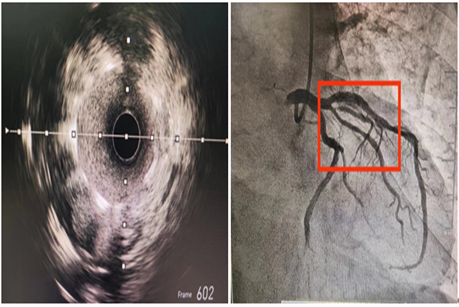

患者为一名老年男性,既往有高血压、高脂血症和长期吸烟史。此次因“冠心病、不稳定性心绞痛”收入我院心内科。冠脉CTA提示:前降支近中段钙化并轻中度狭窄。冠脉造影提示:前降支近中段轻度钙化并临界病变。为精准评估治疗患者的血管病变,我院心内科团队利用IVUS技术精准评估管腔的状况。结果显示,近段测量管腔面积非常狭小,并伴有环形钙化以及明显钙化结节,手术难度极高。

血管内超声是什么?

血管内超声(IVUS)是一种利用超声波技术实时观察血管内部情况的方法,能够提供更准确的成像结果。通过IVUS的精确测量,医生们可以更好地判断血管的病变程度和狭窄位置,从而指导冠状动脉介入术操作,提高手术的安全性和成功率,减少术后并发症。